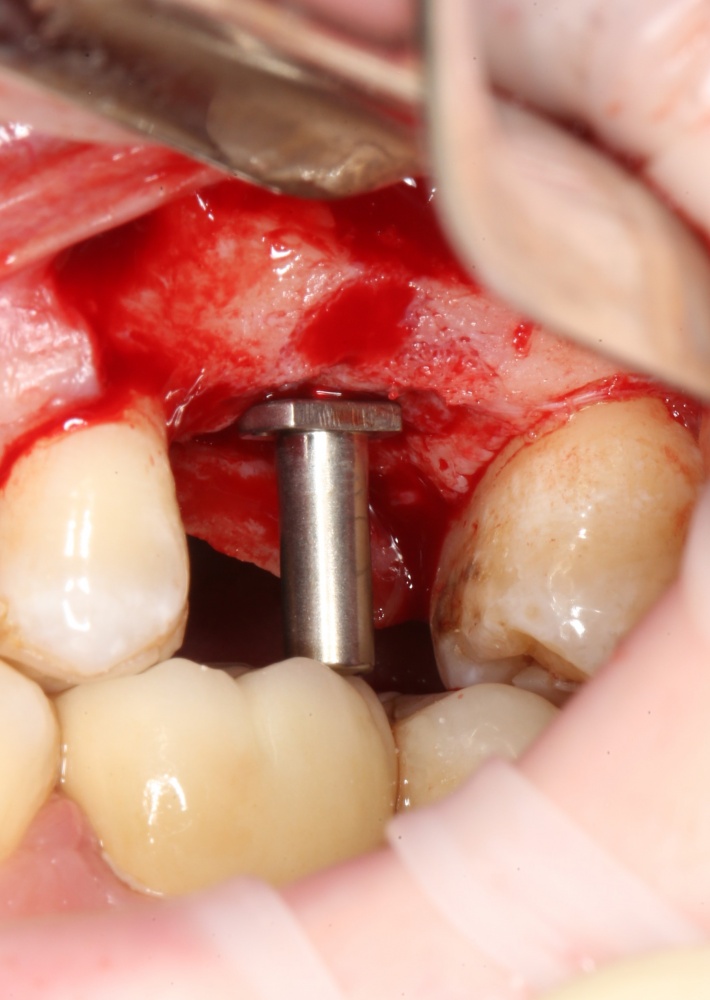

Кстати, комплект поставки не содержит ни заглушки, ни абатмента. А сам имплантат фиксируется на ключе простым заклиниванием платформы. Т. е. не слишком надёжно:

Если лунка подготовлена правильно, то имплантат проваливается в неё почти полностью: